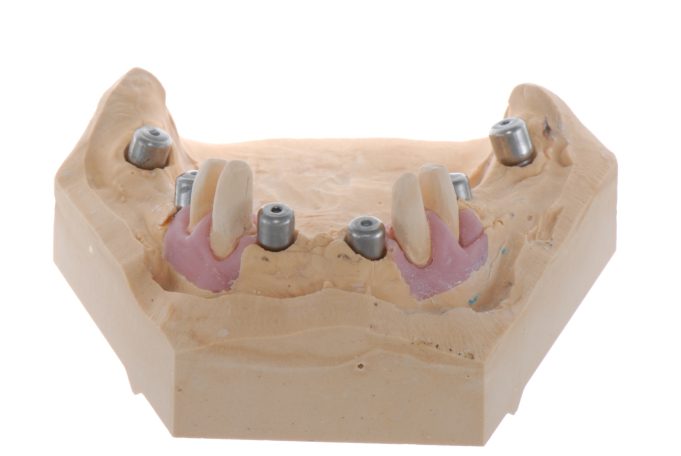

Verschraubte Implantatbrücken fühlen sich für den Patienten an wie die eigenen Zähne.

Implantsteg verankerte Brücke. Für den Patienten abnehmbar, aber der Tragekomfort von festen Zähnen.